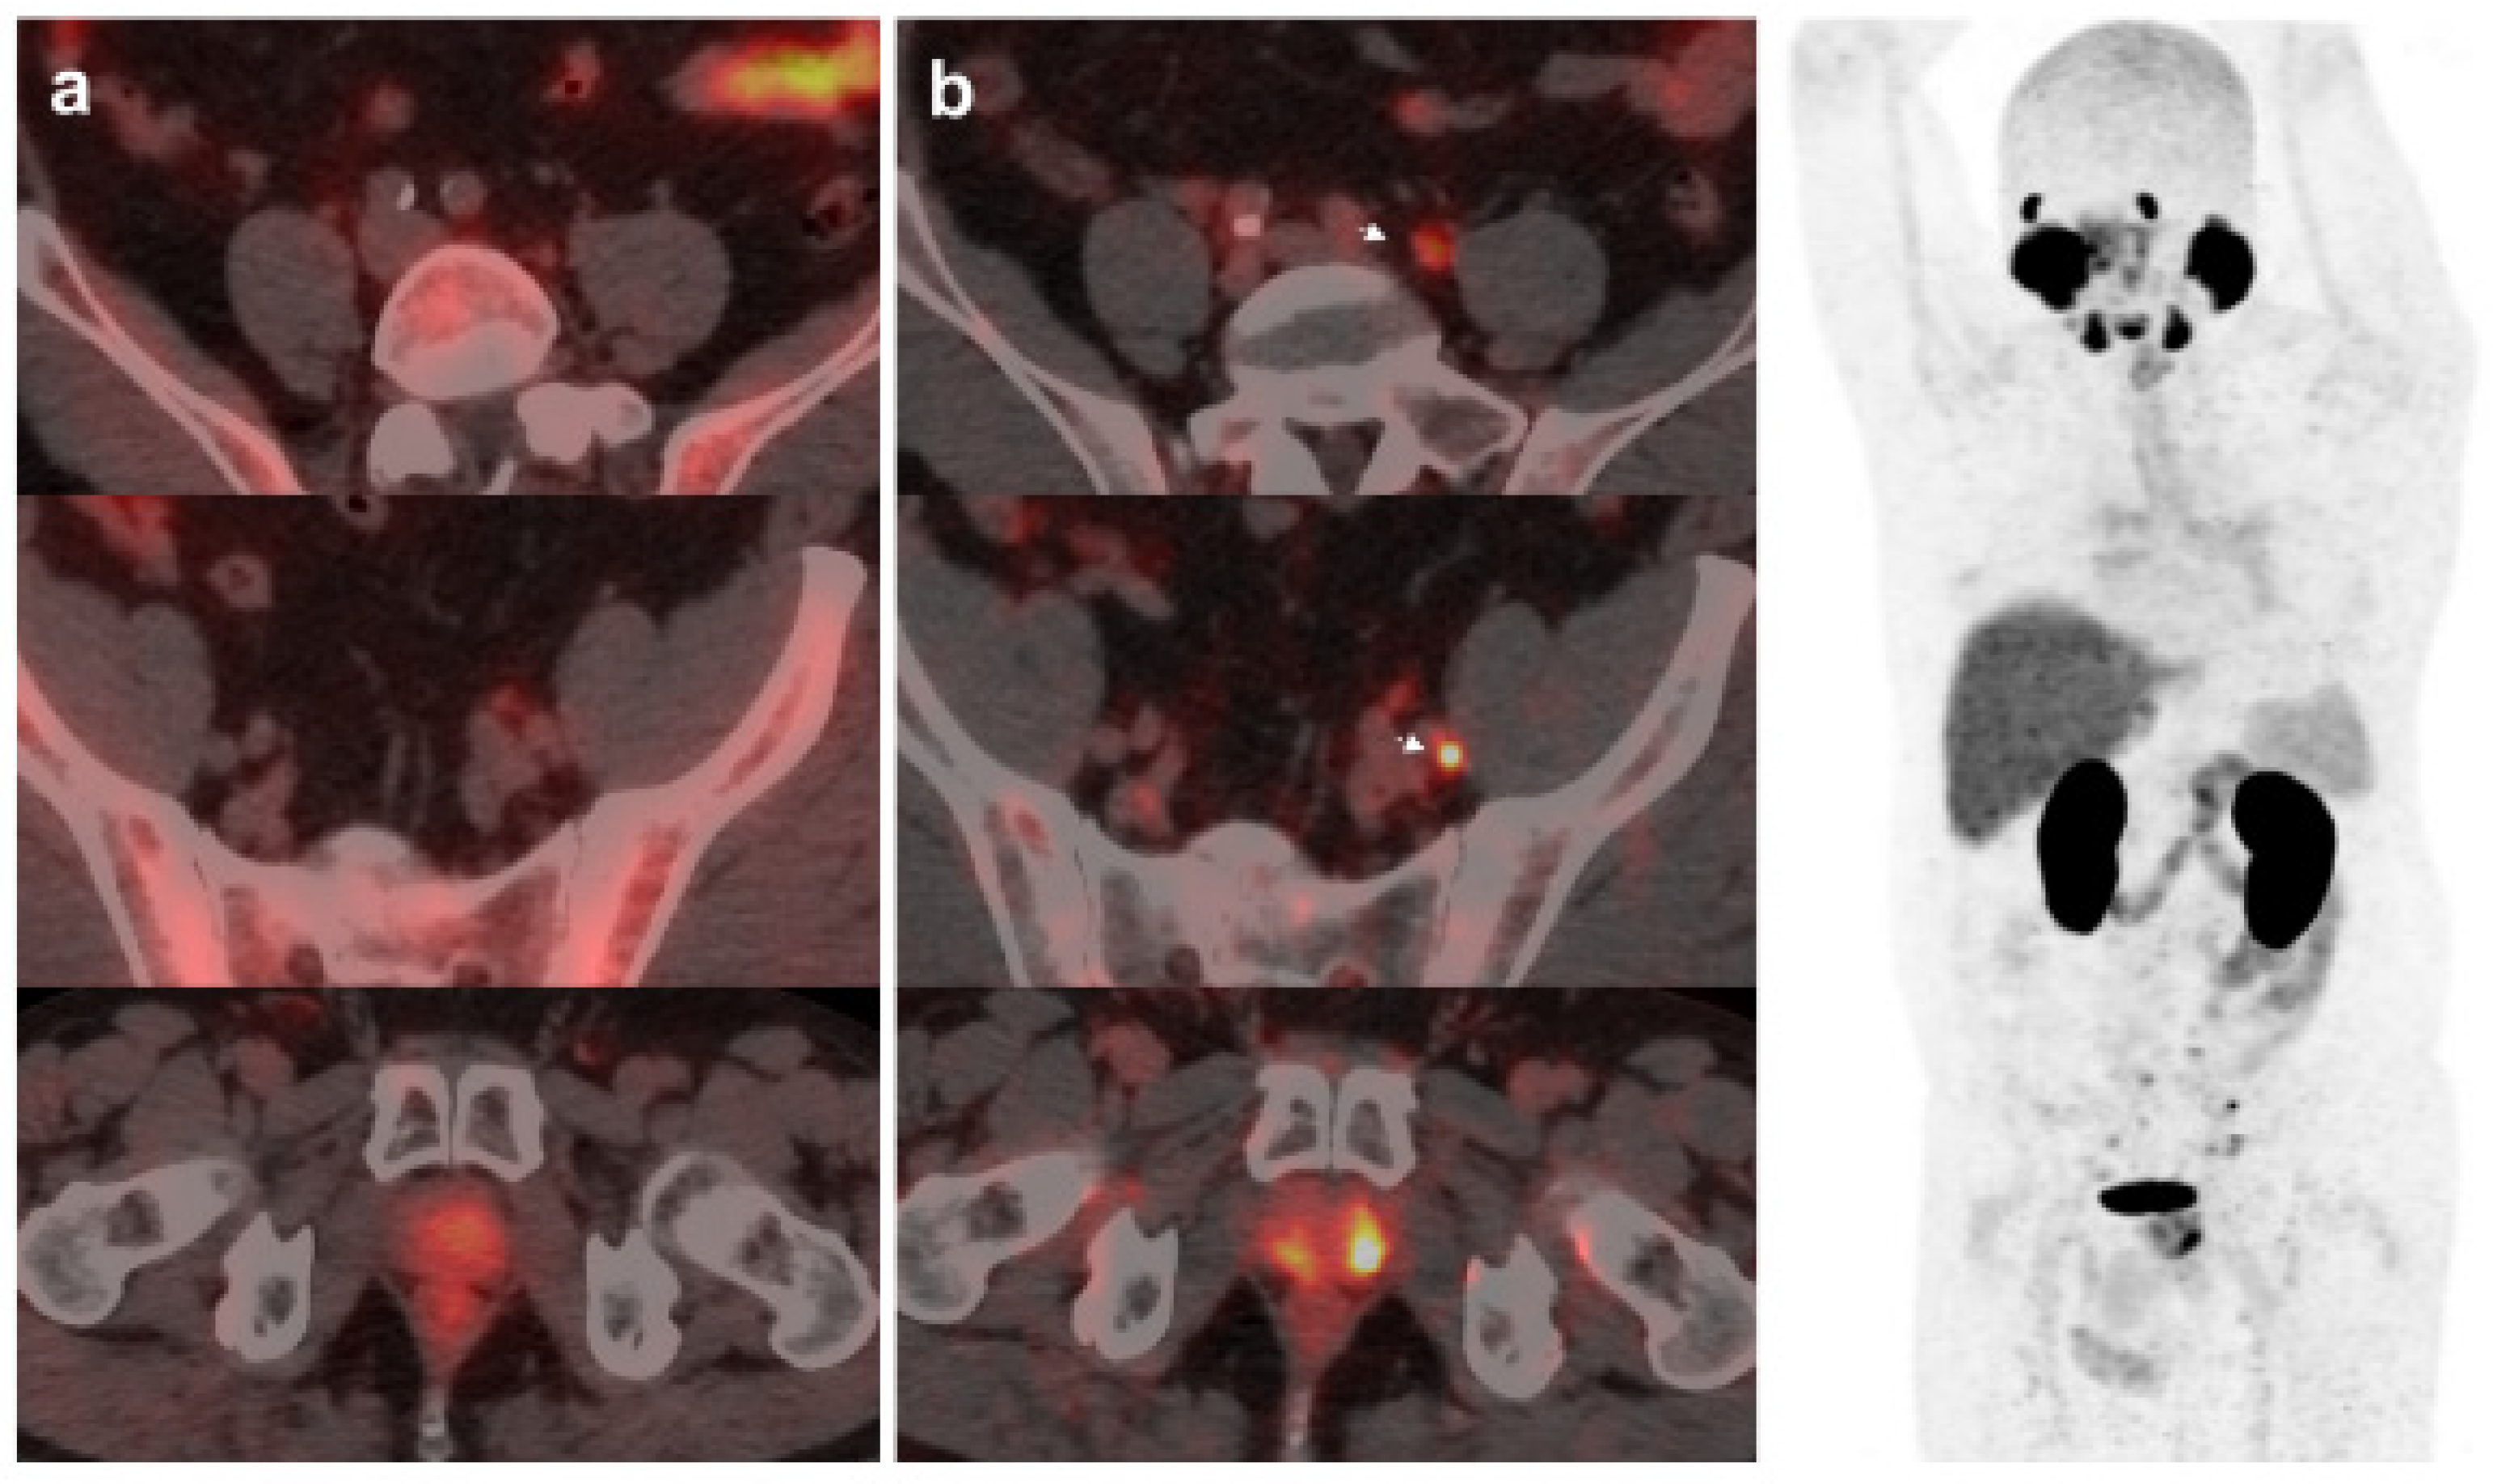

On the other hand, 18F-DCFPyL was positive alone in 48/89 (53.9%) patients, being oligometastatic in 25 (Figure 2). Five patients were exclusively positive with 18F-Fluorocholine-PET/CT, and thus 18F-DCFPyL down-staged 18F-Fluorocholine results from positive to negative (3 follow-up, 1 biopsy (negative) and 1 ADT). 18F-DCFPyL up-staged 5/21 patients with OD on 18F-Fluorocholine-PET/CT to polimetastatic disease after 18F-DCFPyL.

Figure 2. 67-year-old patient. Gleason 7 PCa treated with RP. First BCR treated with prostate fossa radiotherapy. Second BCR (PSA: 0.63 ng/mL, PSAdt 8.6 mo, PSAvel 0.04 ng/mL/mo) scanned with 18F-Fluorocholine (a) and 18F-DCFPyL-PET/CT (b), time window of six days. Lymph nodes metastasis (arrows) were demonstrated only on 18F-DCFPyL scan, changing therapeutic management (escalation). Patient underwent lymph nodes SBRT descending PSA level.